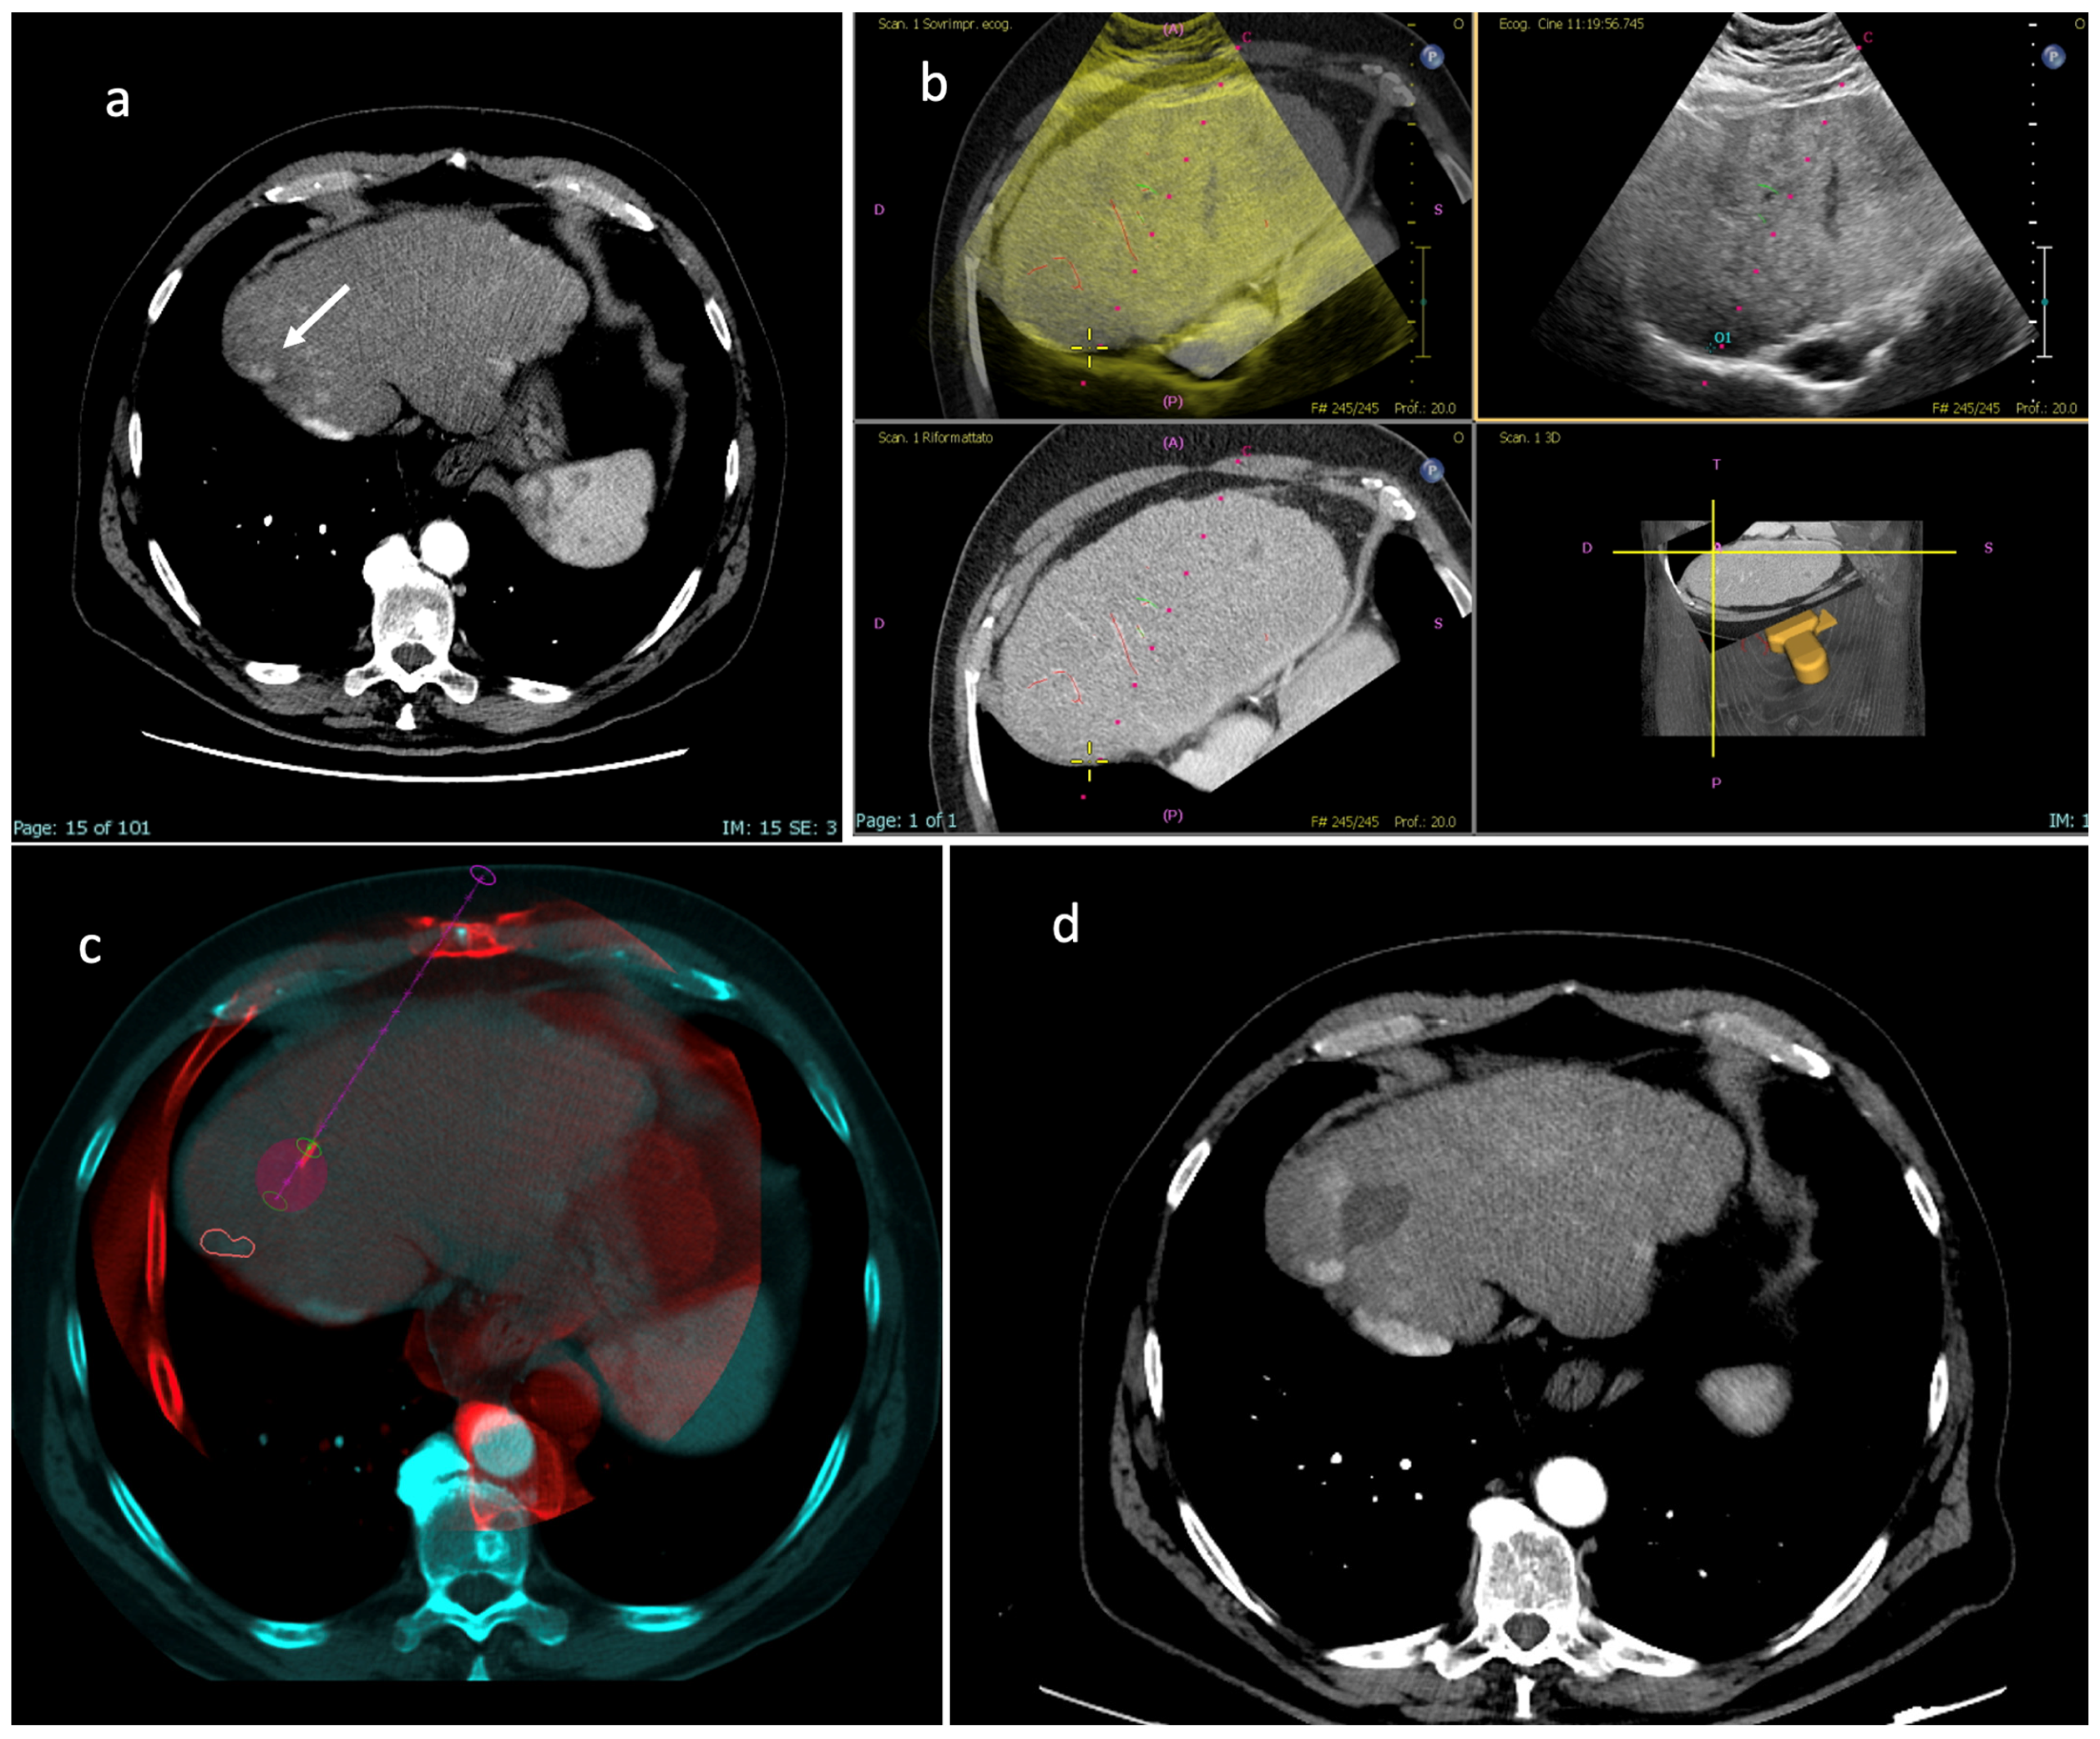

Figure 5. Missed target; (a) Axial CT image in the arterial phase showing a hypervascular nodule in S8, postero-lateral to an ablation volume from previous treatment, consistent with recurrent disease (white arrow). (b) US fusion imaging is performed by registrating pre-procedural CT images to real-time US images, and the antenna is placed within the target tumor. (c) CBCT fusion imaging indicates that the antenna and the predicted ablation volume (purple) are distant from the tumor (red contour), differently from what is suggested by US fusion imaging. Since the registration quality between US real-time images and pre-procedural CT images appeared good, the operator decided to ablate without repositioning the antenna. (d) CT axial image in the arterial phase at 1-month follow-up resulted comparable to intraprocedural CBCT fusion imaging, demonstrating that the nodule was missed.